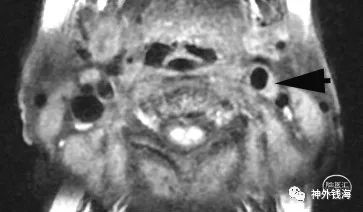

图4 颈动脉高分辨率磁共振可见左侧颈内动脉起始部有明显斑块形成,如箭头所示。颈动脉狭窄程度约50%。这与图1中CTA显示的狭窄程度(20%)差异很大。

我们更信任高分辨率磁共振检查的结果。从以往的经验中,我们认为颈动脉CTA尽管在筛查颈动脉狭窄上有很大优势,但是在判断颈动脉狭窄程度上,没有高分辨率磁共振准确。从术中的实际情况验证来看,CTA容易在某种程度上低估狭窄的实际水平。相比之下,高分辨率磁共振对狭窄程度的判断更接近术中所见的实际情况。